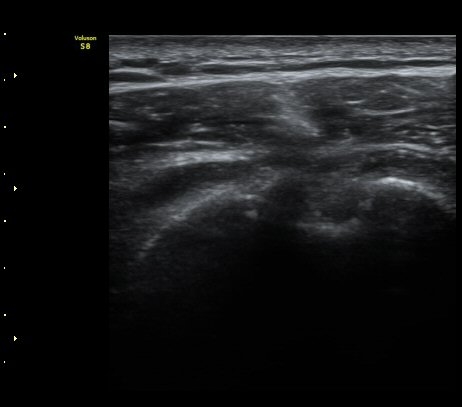

±Ø»ó°Ç ¿ÜÃø Á¾´Ü¸é°Ë»ç ½Ã Á¡¾×³¶ ºÎÁ¾ÀÌ °üÂûµÊ(±×¸² 4).

±Ø»ó°Ç ±ÙÀ§ºÎ ±Ø»ó°Ç ³»ÃøÀÇ Àú¿¡ÄÚ ºÎÁ¾°ú Á¡¾×³¶ ºÎÁ¾ÀÌ °üÂûµÊ(±×¸² 5).